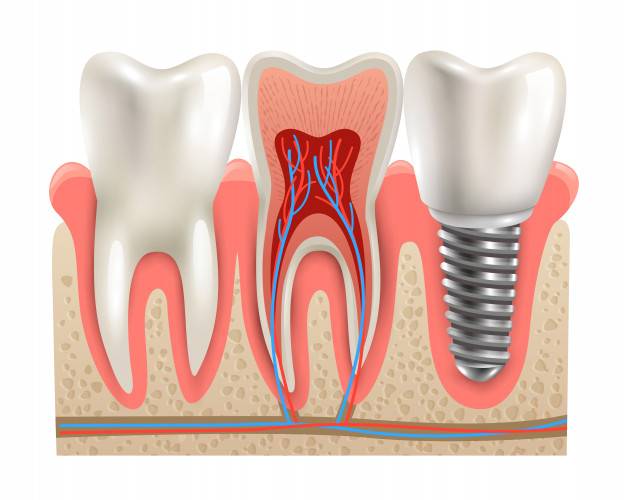

ایمپلنت دندان چیست؟

ایمپلنت دندان یک نوع فرایند دندانپزشکی است که دندان از دست رفته را به طور کامل جایگزین می کنند. همچنین یک تیتانیوم کوچک است که دندانپزشکان از داخل روی فک قرار می دهند. اینکه دندانپزشک ایمپلنت دندان را چگونه انجام دهد، بستگی به وضعیت استخوان فک و نوع ایمپلنت دارد.

جراحی ایمپلنت دندان معمولاً خیلی طولانی نیست و مزیت بزرگ ایمپلنت ها این است که می تواند جایگزین کامل برای دندان از دست رفته باشد. فقط بعد از انجام این جراحی باید صبر کنید تا ایمپلنت به طور کامل داخل لثه سفت شود و استخوان بهبود پیدا کند که معمولاً به چند ماه زمان نیاز دارد.